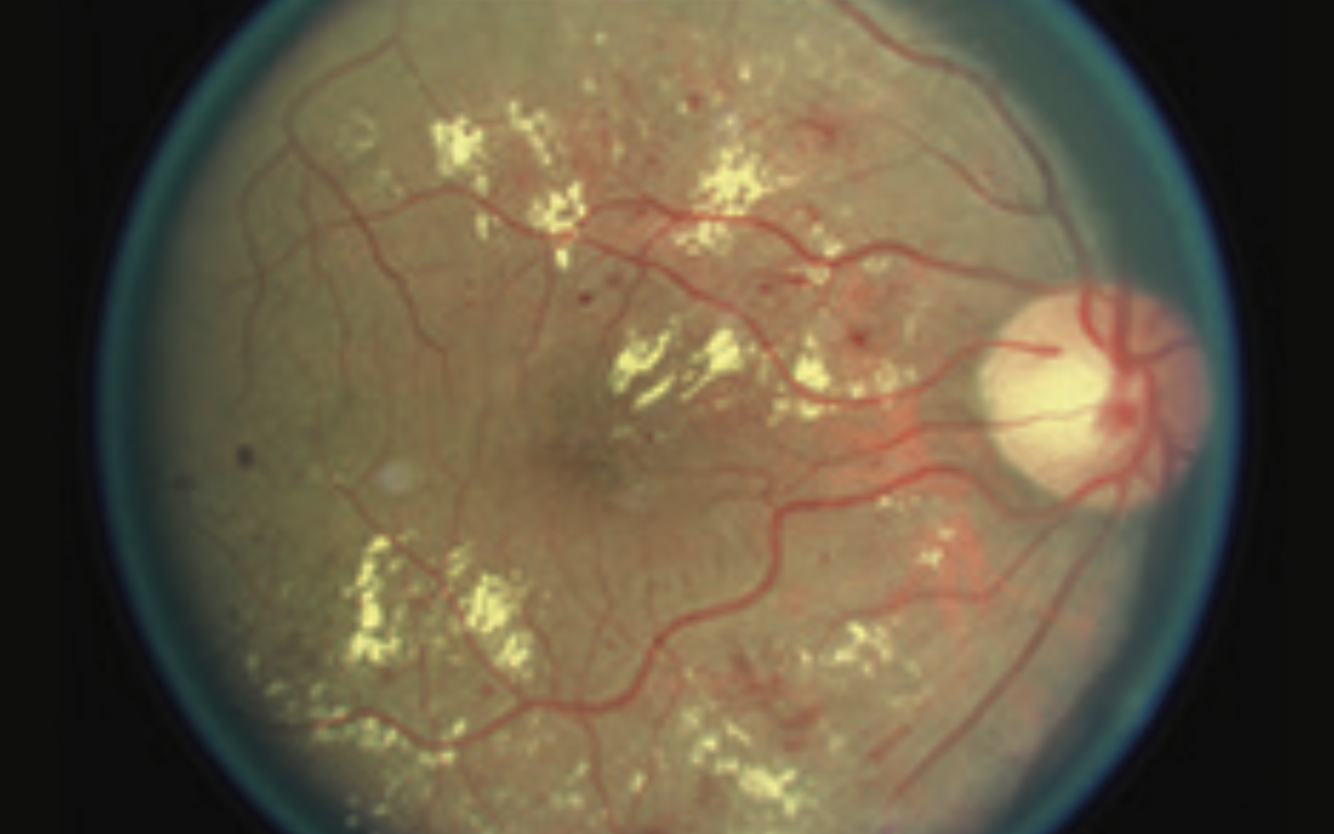

Pre-proliferative Diabetic Retinopathy

-cotton wool spots

- dot and blot haemorrhages